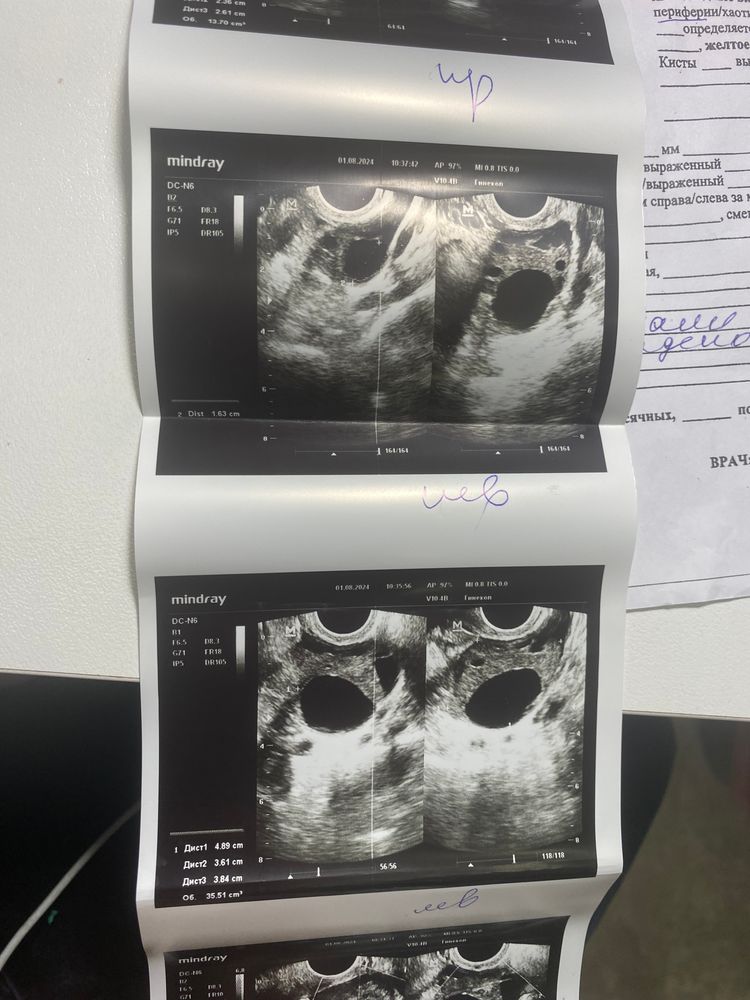

Овуляция( тесты на овуляцию)Девочки, сходила на узи сегодня (21 дц). Правый яичник немного увеличен, узист сказала, что овуляция была справа, но когда точно сказать не может. И что то сказала про желтое тело. Посмотрела я результаты узи, именно формулировки желтое тело не увидела. Зато она написала постовуляторный фолликул, это она так описала желтое тело ? В инете нашла только 1 статью где также пишут про желтое тело. И вот думаю теперь 🤔

Екатерина Журавлева, может. Значит, что овуляция у Вас была в левом яичнике. Если Б наступила, то оно не будет уменьшаться. Если Б не наступила, то к концу цикла жёлтое тело начнет уменьшаться.